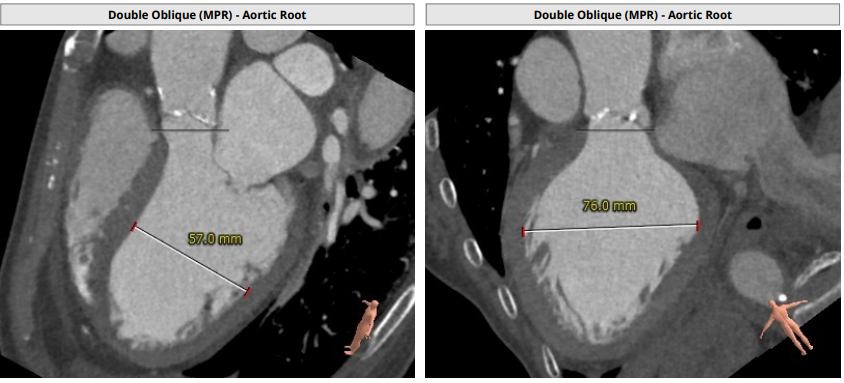

术前CT分析:

· 三叶瓣,中度钙化。整体结构呈上小下大,法式窦结构小,左冠瓣叶长度较长,流出道大。

瓣环平均直径:24.0mm,左室流出道平均直径:25.2mm

左冠窦:25.5mm,右冠窦:22.6mm,无冠窦:28.7mm,

窦管交界处:22.9mm

升主未见明显增宽:34mm,心脏角度:41°

钙化积分:501mm³,中重度钙化

左冠高度:10.9mm,右冠高度12.7mm

心室明显增大